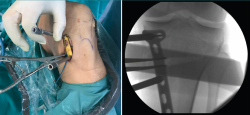

Posteriormente, bajo control radioscópico, se realiza la osteotomía apoyando la sierra por debajo de la aguja guía, llegando hasta 1 cm de la cortical lateral. Se introducen los escoplos para abrir la osteotomía (Figura 4). El primer escoplo, el más ancho, se introduce primero para comprobar el corte completo de la cortical posterior. Seguidamente, se coloca el medidor del ángulo de apertura (Figura 5A) y, a continuación, se introduce el distractor en la parte posterior de la osteotomía, evitando así un aumento de la PTP (Figura 5B). En este momento, se puede introducir en la apertura de la osteotomía el aloinjerto o sustituto óseo. Los autores utilizan aloinjerto óseo cuando la apertura es mayor de 10°. Antes de colocar y fijar la placa de osteotomía, se realiza el túnel tibial utilizando las herramientas artroscópicas clásicas (Figuras 6A y 6B). Al realizar una osteotomía biplanar, el corte es suficientemente distal como para permitir brocar el túnel tibial de la RLCA sin dificultades.

Figura 4. Colocación de escoplos de forma progresiva para realizar la apertura (una vez realizados los cortes con la sierra).

Una vez hecho el túnel tibial, se introduce la plastia y se fija a nivel femoral y tibial (Figura 7). Si se utiliza una plastia de isquiotibiales, los autores recomiendan una fijación femoral cortical de suspensión regulable, dejando unos milímetros para el ajuste final después de la colocación de la placa de osteotomía. Una vez fijada la plastia, se procede a la colocación de la placa de osteotomía TomoFix® (Synthes, Oberdorf, Switzerland) para la tibia proximal medial (Figura 8). En la mayoría de los casos el tornillo más anterior coincide con el túnel tibial de RLCA, motivo por cual no se coloca (Figura 9).

Figura 5. A: medición del ángulo de apertura de la osteotomía con el medidor; B: colocación del distractor en la parte posterior de la osteotomía, evitando así el aumento de la pendiente tibial posterior.

Figura 6. A: colocación de la aguja guía para realizar el túnel tibial; B: brocado del túnel tibial. Se observa el espacio metafisario suficiente para realizar el túnel tibial, sin interferencias con la osteotomía.

Figura 7. Introducción de la plastia a través del túnel tibial, manteniendo el distractor en posición.

Figura 8. Colocación de la placa TomoFix® para la tibia proximal medial una vez fijada la plastia de ligamento cruzado anterior a nivel femoral y tibial.

Figura 9. Fijación de la placa con tornillos. Se señala con la flecha la ausencia del tornillo más anterior, dada su coincidencia con el túnel tibial.